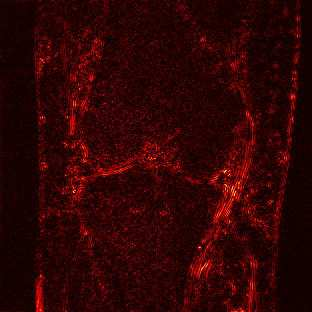

Limited by imaging systems, the reconstruction of Magnetic Resonance Imaging (MRI) images from partial measurement is essential to medical imaging research. Benefiting from the diverse and complementary information of multi-contrast MR images in different imaging modalities, multi-contrast Super-Resolution (SR) reconstruction is promising to yield SR images with higher quality. In the medical scenario, to fully visualize the lesion, radiologists are accustomed to zooming the MR images at arbitrary scales rather than using a fixed scale, as used by most MRI SR methods. In addition, existing multi-contrast MRI SR methods often require a fixed resolution for the reference image, which makes acquiring reference images difficult and imposes limitations on arbitrary scale SR tasks. To address these issues, we proposed an implicit neural representations based dual-arbitrary multi-contrast MRI super-resolution method, called Dual-ArbNet. First, we decouple the resolution of the target and reference images by a feature encoder, enabling the network to input target and reference images at arbitrary scales. Then, an implicit fusion decoder fuses the multi-contrast features and uses an Implicit Decoding Function~(IDF) to obtain the final MRI SR results. Furthermore, we introduce a curriculum learning strategy to train our network, which improves the generalization and performance of our Dual-ArbNet. Extensive experiments in two public MRI datasets demonstrate that our method outperforms state-of-the-art approaches under different scale factors and has great potential in clinical practice.